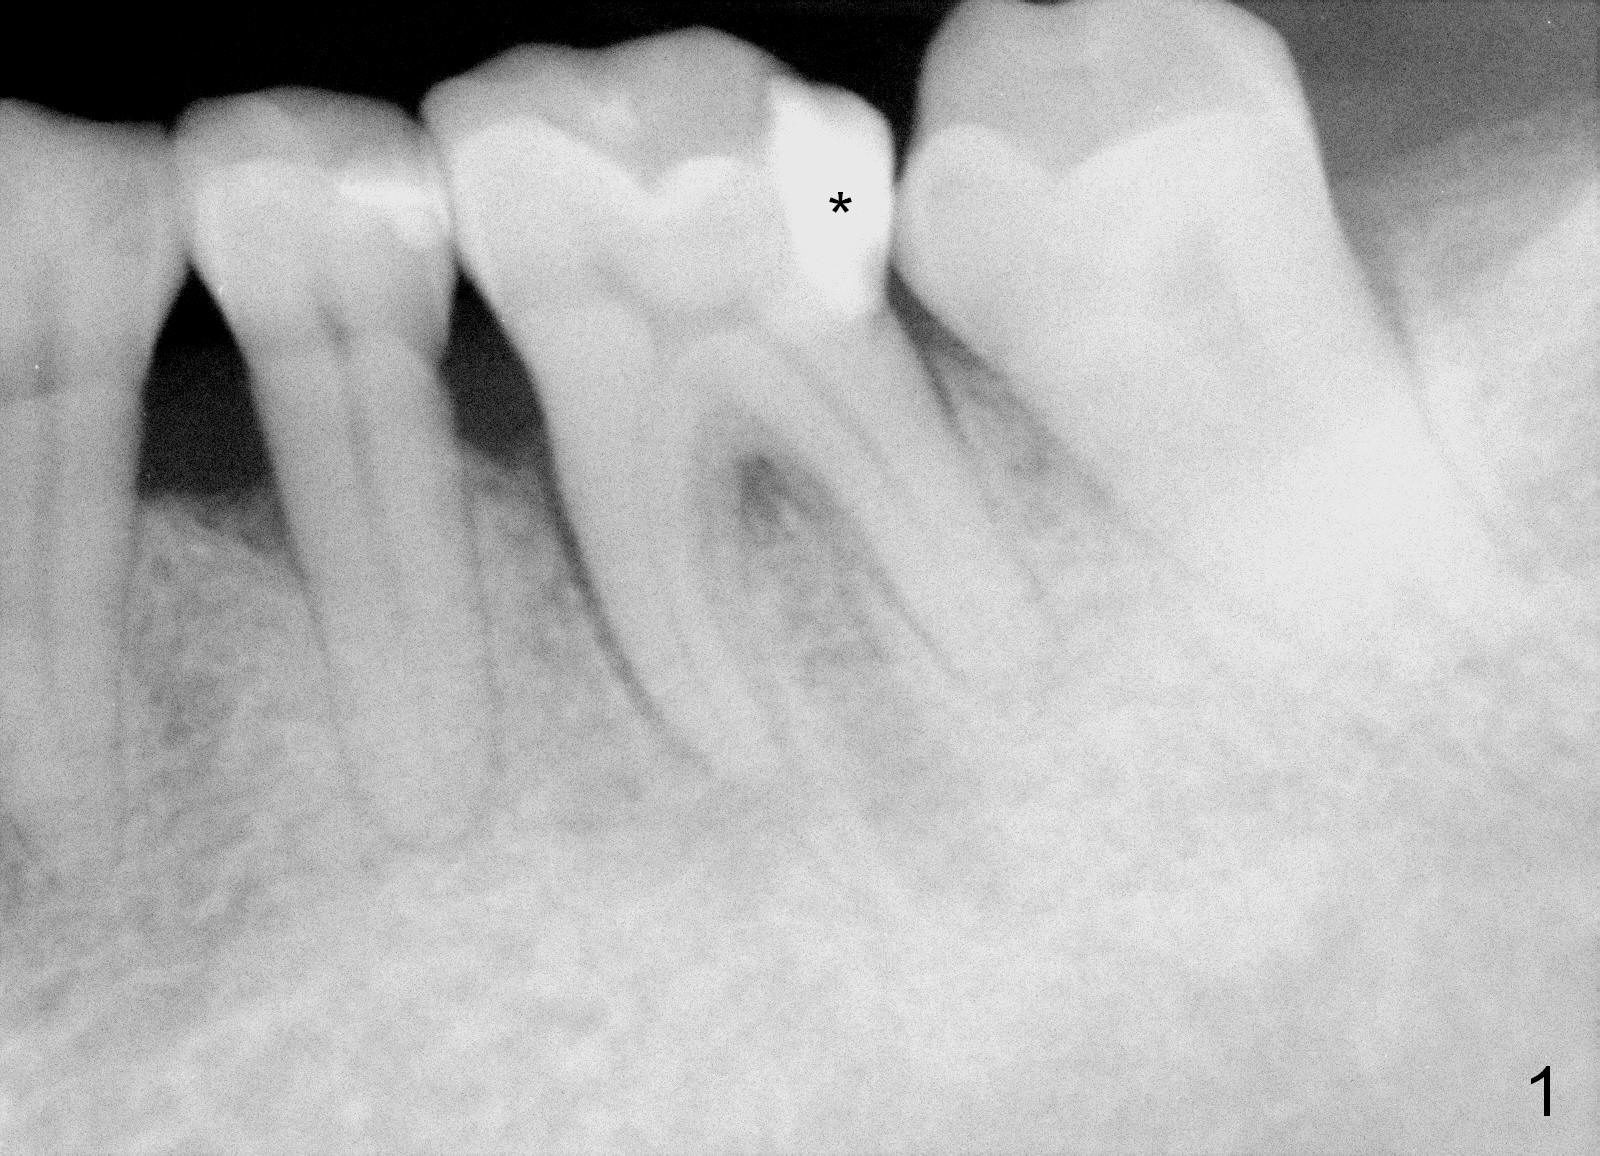

A 59-year-old lady has history of periodontal disease and bruxism.  The tooth #19 has pulpitis after unsuccessful DO composite (Fig.1 *) and requires root canal therapy (Fig.2).  Six months later, a fistula is found to communicate with the furca (Fig.3 *: gutta percha).  Less than 3 years, the furca enlarges with symptoms of infection (Fig.4 *).  She works out of state. The Principle of No Implant, No Extraction is adhered.  Since she is of short statue, the bone height is relatively limited.  A 6x14 mm tissue-level implant is appropriate (Fig.5, one piece).  Sensor 1 may be proper for her small mouth.  When the bottom of the socket is large and close to the Inferior Alveolar Nerve, can an immediate implant be placed?